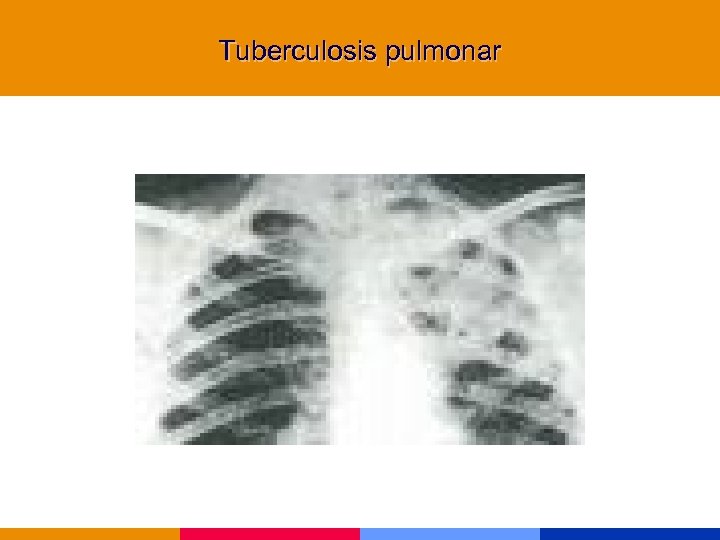

Tuberculosis § La infección por HIV predispone a TBC, y ésta deteriora la evolución de la infección por HIV § Presentación clínica depende del nivel de inmunocompromiso • CD 4 >300 mm 3 similar a huésped normal con fiebre, tos productiva, hemoptisis, pérdida de peso y cavitación • CD 4 <200 mm 3 atípca con frecuente compromiso extrapulmonar, enfermedad miliar y ausencia de tos.

Tuberculosis § La infección por HIV predispone a TBC, y ésta deteriora la evolución de la infección por HIV § Presentación clínica depende del nivel de inmunocompromiso • CD 4 >300 mm 3 similar a huésped normal con fiebre, tos productiva, hemoptisis, pérdida de peso y cavitación • CD 4 <200 mm 3 atípca con frecuente compromiso extrapulmonar, enfermedad miliar y ausencia de tos.

Tuberculosis § PPD positiva sólo en 30 a 50% de los pacientes. § Rx tórax: opacidades intersticiales o lobares, perihiliares. § Esputo: sensibilidad similar a pacientes HIV negativos § Tratamiento empírico inicial: se acepta en espera de resultados de cultivos.

Tuberculosis § PPD positiva sólo en 30 a 50% de los pacientes. § Rx tórax: opacidades intersticiales o lobares, perihiliares. § Esputo: sensibilidad similar a pacientes HIV negativos § Tratamiento empírico inicial: se acepta en espera de resultados de cultivos.

Tuberculosis pulmonar

Tuberculosis pulmonar

Tuberculosis pulmonar

Tuberculosis pulmonar